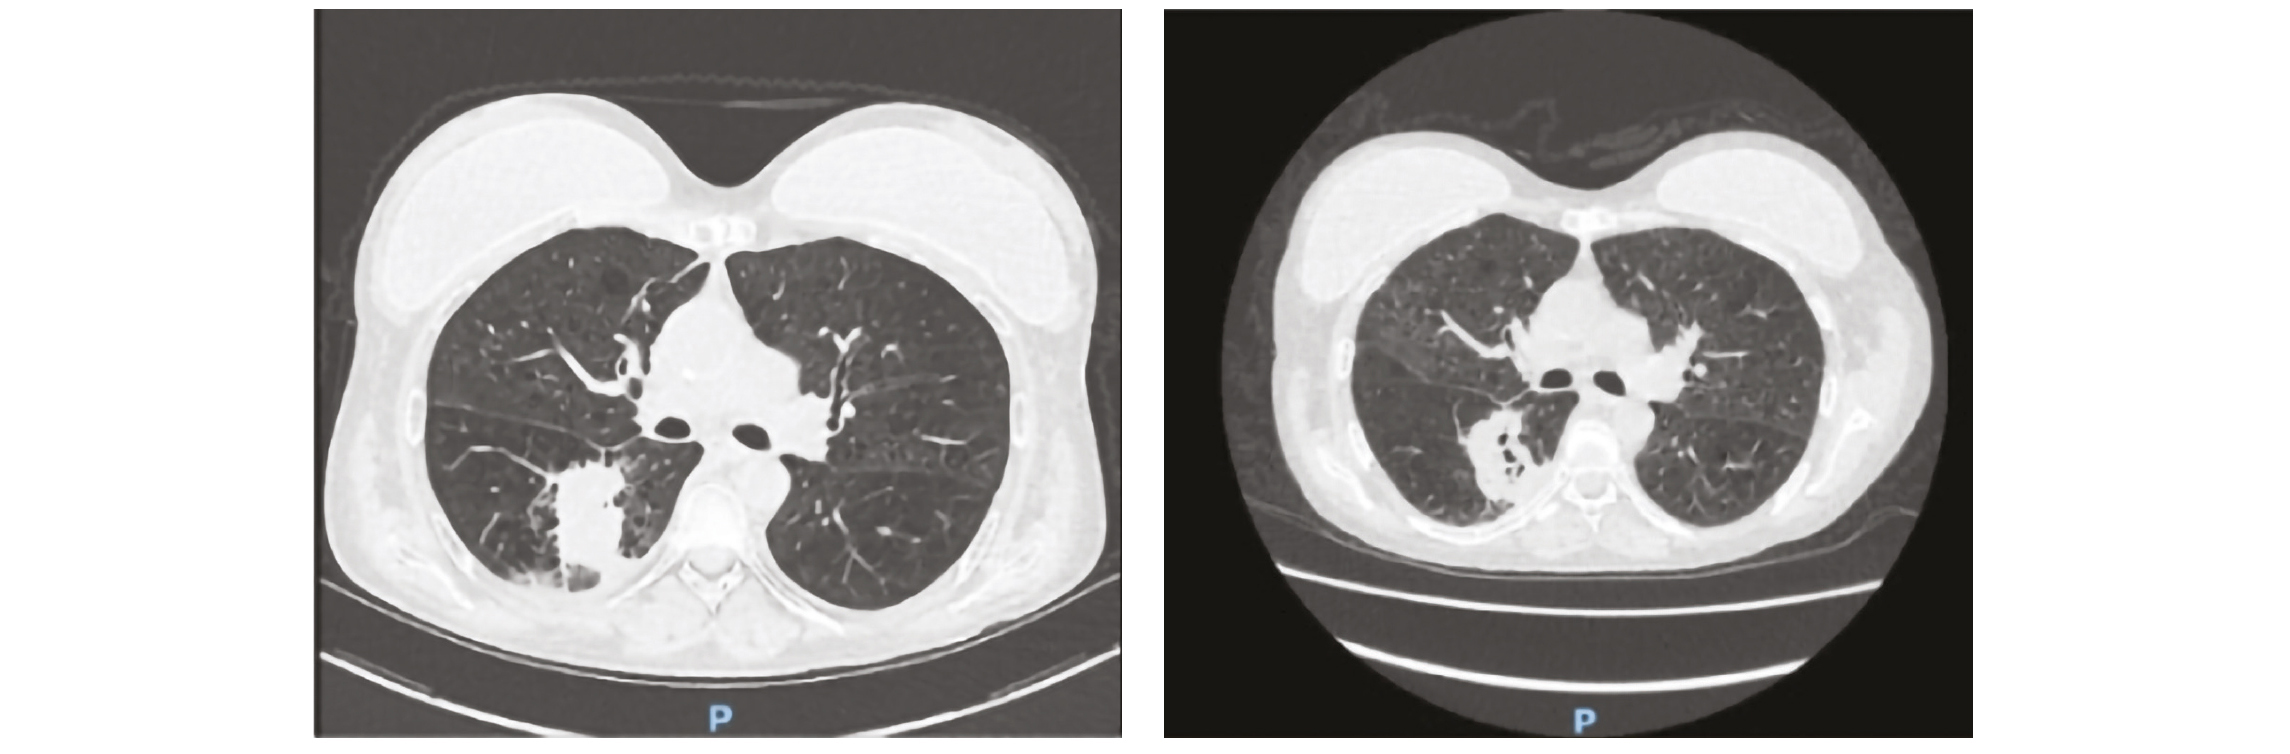

Les signes radiologiques à rechercher par TDM-thoracique injectée sont : opacités alvéolaires, infiltrats ou nodules aspécifiques, “halo sign (foyer d'infarctus périlésionnel), puis à une phase plus tardive : un “air-crescent sign” (cavitation avec croissant gazeux périphérique) (5, 6).

Patient avec diagnostic API

Imagerie au diagnostic (à droite) puis à J10 du traitement antifongique (à gauche)